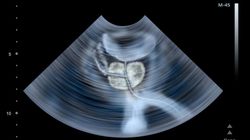

Prostata - leczenie operacyjne

Jestem mężczyzną - mam 66 lat. Mam PSA na poziomie 12. Miałem pobieraną biopsję igłową i wynik jest: adenocarcinoma prostate. Gleason 2+2. Płat lewy: 456 (1)(1c), 457 (2)(4)(5)(3c), 458 (3)(1c). Płat prwy: 459(1)(1c) +s, 460(2)(1c), 461 (3)(1c), 462 (4)(1c), 463 (5)(2c). Lekarz urolog zdecydował, żeby usunąć chirurgicznie ten gruczoł. Czy to może być dobra decyzja, czy jest możliwość jeszcze leczenia farmakologicznego?